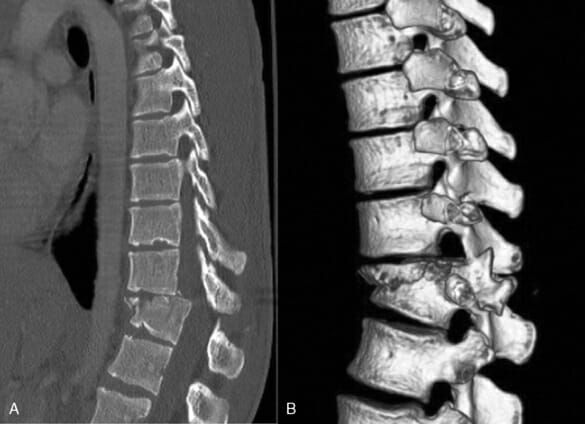

CT กระดูกสันหลัง (Computed tomography scan)

จริงๆแล้วการทำ CT scan ก็เป็นการใช้รังสี X-ray ในการตรวจวินิจฉัยเช่นเดียวกัน แต่เป็นการใช้เครื่องตรวจพิเศษที่จะทำการยิงลำแสง X-ray ออกมาในหลายทิศทางพร้อมๆกัน และใช้เครื่อง Computer ในการประมวลผลเพื่อสร้างออกมาเป็นภาพ 2D และ 3D

การตรวจ CT scan ในแง่ของโรคทางกระดูกสันหลังนั้นมักทำในผู้ป่วยที่คิดว่ามีการแตกหักของกระดูก การติดเชื้อ มีก้อนเนื้องอก และทำเพื่อวางแผนการผ่าตัดในเคสที่แพทย์คิดว่ามีความซับซ้อนในการผ่าตัดสูงกว่าปกติเป็นต้น โดยในปัจจุบันเทคโนโลยี CT scan สมารถสร้างภาพออกมาเป็น 3 มิติได้แล้วนะครับ ซึ่งทำให้แพทย์ทำงานได้ง่ายมากขึ้นทีเดียวครับ

การตรวจ CT scan สามารถทำได้รวดเร็วและใช้เวลาไม่นานอย่างที่หลายคนคิดนะครับ โดยปกติจะใช้เวลาในการอยู่ในเครื่องสแกนไม่เกิน 5-10 นาทีเท่านั้นเอง

ในส่วนข้อควรระวังและข้อจำกัดในการทำ CT scan จะคล้ายกับการตรวจ X-ray เพราะเป็นการใช้คลื่นรังสี X เช่นเดียวกันและใช้ในปริมาณที่มากกว่ามาก รวมทั้งค่าใช้จ่ายในการทำก็สูงกว่า X-ray หลายเท่าตัวครับ